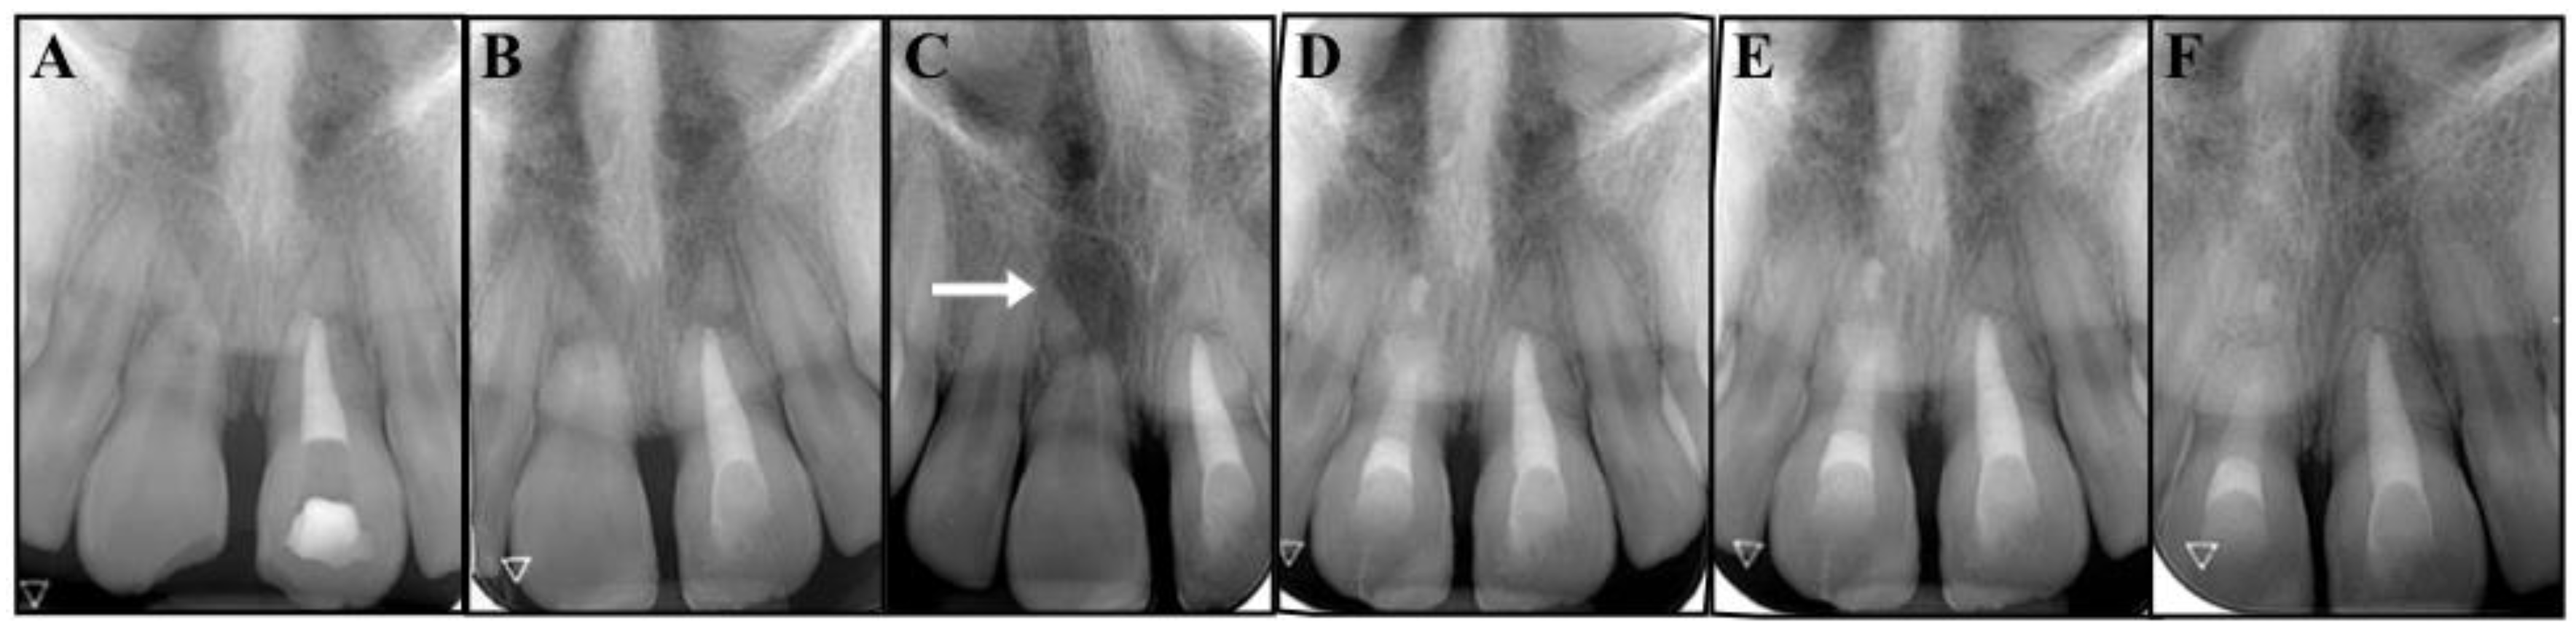

Figure 3.

(A) Root canal filling with of tooth #2.1. (B) Post obturation and restoration of tooth #2.1. (C) The 6-month follow-up periapical radiograph reveals the radiolucency of tooth #1.1 (arrow). (D) Root canal filling with Portland cement and resin restoration of tooth #1.1. (E) Image from the 12-month follow-up. (F) Image from the 30-month follow-up.

Six months later, tooth #1.1 no longer responded to the sensitivity tests and the periapical radiograph showed a radiolucent area at the fracture site of the root (Figure 3C).

Tooth #1.1 was diagnosed with pulp necrosis and apical periodontitis in the coronal fragment, and an apexification procedure was performed with the same protocol as the one previously described for tooth #2.1 (Figure 3D). We then filled the canal with Portland cement (Aureoseal, Ogna lab, Muggiò, Italy).

The follow-up was carried out according to schedule. At 30 months, the patient was free of symptoms, and the periapical radiographs showed healthy periodontal tissues around both the fractured roots and the apical fragments, while the fractured areas seemed to have healed, with hard tissue deposition (Figure 4C,D). The tooth eruption was assessed to be normal with the continued development of the alveolar ridge. Undesirably, tooth # 2.1 showed mild signs of discoloration. The patient was informed that the clinical and radiographic follow-up would continue once a year for at least another three years, and ideally for as long as possible. She was also made aware that further considerations will be necessary upon completion of the permanent dentition.

Figure 4.

(A,B) Clinical photograph and intraoral radiographs of teeth #1.1 and #2.1 at the initial stage of treatment (replantation) and at the 30-month follow-up. (C,D) The images show good coronal restorations, mild signs of discoloration in the cervical portion of tooth #2.1, healing in the fracture lines, a healthy periapex.

The complexity of this case derives from the combination of root fractures with the avulsion of the coronal fragments, which places the traumatic injury into two different categories (Figure 1B). Fortunately, it was possible to merge the recommendations [1,2,13] and provide a reasonable treatment plan. At 30 months, the patient was asymptomatic, the replanted fragments did not exhibit mobility or a metallic percussion sound, and radiographs showed no evidence of infection-related or ankylosis-related resorption. The application of an apexification treatment to the coronal segments has enabled the healing of apical periodontitis and the repair of the fractured ends of the roots, while the apexes seem to have maintained their vitality, as shown by the lack of symptoms and clinical and radiographic signs (Figure 4C,D). The only unfavorable outcome was represented by a mild discoloration detected in the cervical area of tooth # 2.1.